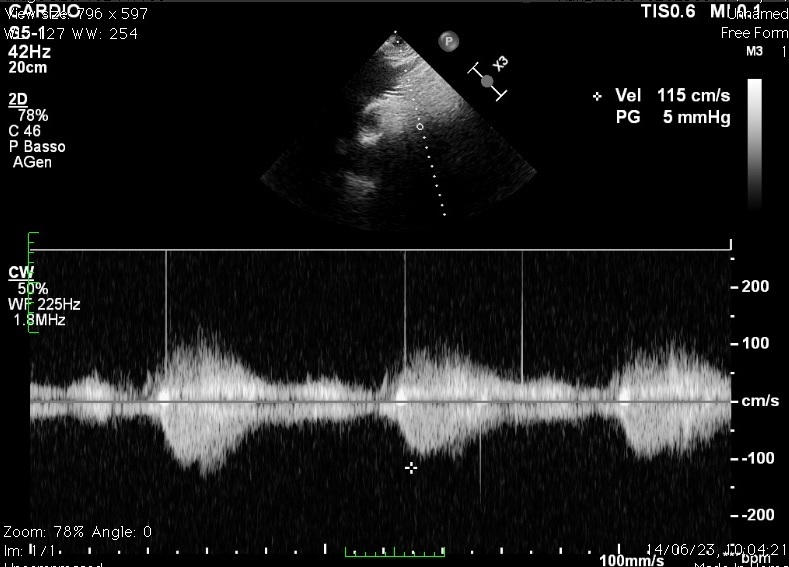

An 80-year-old man was referred to our cath-lab for transcatheter aortic valve implantation (TAVI) due to symptomatic severe aortic valve stenosis. The intervention utilized a balloon-expandable prosthesis (Sapien 3 Ultra n°26, Edwards Lifesciences). An unexpected pop-out with device dislodgement in the ascending aorta occurred during implantation (Video 1). The prosthesis was repositioned distally in the aortic arch using an Amplatz Goose Neck snare catheter (Medtronic), maintaining supra-aortic vessel patency (Video 2). Stability was ensured by inflating a 28 mm balloon (Video 3), followed by the introduction of a second Sapien 3 Ultra n°26 prosthesis through the first (Video 4). The latter was successfully implanted with favorable angiographic results (Video 5). Subsequently, marked differential blood pressure values between the upper and lower limbs were observed, accompanied by acute kidney injury. Computed tomography (CT) multi-projection reconstruction images revealed reversed prosthesis leaflets (Figure 1) and a high transaortic gradient on transjugular Doppler-ultrasound (Figure 2), indicating acute iatrogenic aortic coarctation. Aortic stenting-in-valve using a 26 mm Numed Mounted CP Stent was performed (Video 6), promptly normalizing the transaortic gradient (Figure 3) and leading to clinical improvement. To the best of our knowledge, this is the first reported case of acute iatrogenic aortic coarctation following prosthesis pop-out during TAVI, suggesting that prosthesis rotation and subsequent leaflets reversion were responsible for the intraluminal obstruction.